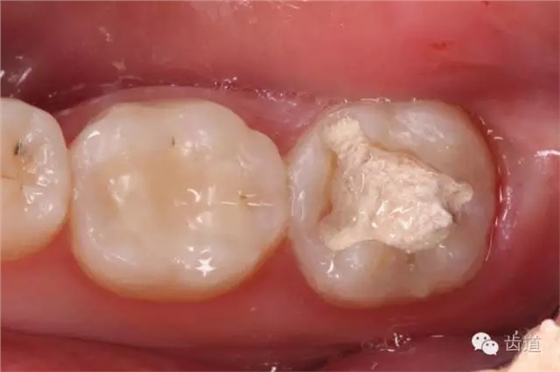

10. 術(shù)后即刻口內(nèi)照片

檢查:術(shù)后半年回訪,37牙體及合面嵌體未見(jiàn)缺損及裂紋,邊緣密合,未探及繼發(fā)齲,探痛-,叩痛-,松動(dòng)-,冷水刺激痛-,未探及牙周袋及附著喪失,牙齦無(wú)紅腫,X線片檢查示根尖周膜連續(xù)性恢復(fù),根尖周透射影消失。